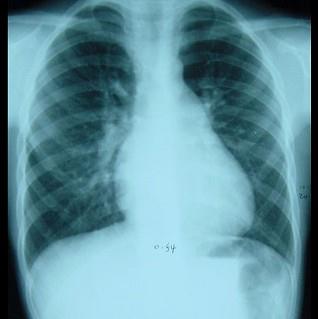

问题 男性,8岁,生后发现心脏杂音,位于胸骨左缘第二肋间,为Ⅲ/6级收缩期杂音,P2亢进,心电图提示不完全性右束支传导阻滞,于前天拍摄心脏正位片,如图所示,下面对心脏片描述正确的是 ( )

选项 A、肺血少,肺动脉段凸出 B、以上均错 C、肺血多,肺动脉段凸出 D、肺血少,主动脉结凸出 E、肺血多,主动脉结凸出

答案 C